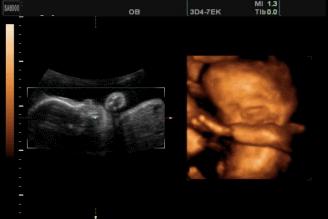

导读:怀孕五个半月,胎儿会笑吗?为什么?

苗苗怀孕5个半月的时候去做四维彩超,她一直注视着大屏幕上宝宝的一举一动。忽然,她看到胎宝宝咧嘴笑了,这给她大大的惊喜,同时,她又很惊讶,宝宝在肚子里也会笑?常听说宝宝出生后还不会笑呢?

其实,关于胎宝宝在肚子里微笑,类似的报道并不少见,很多妈妈反馈过做四维时看到宝宝笑的样子,国外媒体也经常报道类似的新闻。

2003年,英国《卫报》报道,科学家用4D超声波成像系统拍到了26周宝宝微笑的图片。

2018年,英国《每日邮报》报道,一对夫妇在做四维彩超时发现宝宝咧嘴微笑,让父母感到喜出望外。

见诸各大网站的3D胎儿图像,也展示了胎儿在19周时微笑的模样,栩栩如生,惹人喜爱。

怀孕5个半月,胎儿已经有了面部表情,喜怒哀乐都会有,当然胎儿也会发笑。

5个半月的胎儿相当于22周,眼睛、鼻子、眉毛、耳朵、嘴巴等五官面貌结构完整,嘴巴、眉毛活动自如,面部表情丰富也很正常。

从这里看出,在做四维彩超的时候很容易捕捉到胎儿的微笑,这时不要觉得奇怪,这是胎儿正常的生理反应。